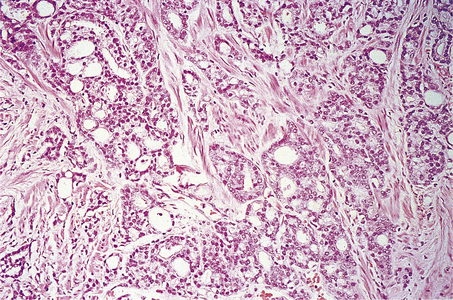

The great majority of tumours are adenocarcinoma, often described as microacinar, though much variety of histological pattern is recognised, and the tumours often show more than one pattern. Rare subtypes include an aggressive small cell carcinoma, which is similar to small cell lung cancer (Ch. 14), and large duct carcinoma, which arises centrally from the large ducts; these are not discussed further.

The Gleason grading system describes the usual patterns taken by the tumour. Gleason pattern 3 is the commonest pattern, and comprises separated, somewhat irregular, gland or acinar profiles, that infiltrate into normal glands at the edge of the mass. Gleason pattern 4 has fused glands or cribriform structures (Fig. 20.11), while in pattern 5 acinar differentiation is no longer apparent in strands of tumour cells, or there may be cribriform structures with central necrosis. It is now widely acknowledged that Gleason pattern 1 is probably not carcinoma, while pattern 2 is a generally small, well-circumscribed mass of regular glands; it is of limited clinical significance. The grading system is to note the dominant (primary) pattern and add the next most frequent (secondary) pattern to give a combined score; where only one pattern is seen (as often applies in a small biopsy) the number is doubled. Thus, the majority of prostate cancers are graded as Gleason 3+3=6; many are Gleason 3+4=7, while a particularly aggressive tumour would be Gleason 5+5=10.

image

Fig. 20.11 Histology of prostatic carcinoma. The tumour is an adenocarcinoma consisting of neoplastic glands infiltrating a fibrous stroma.